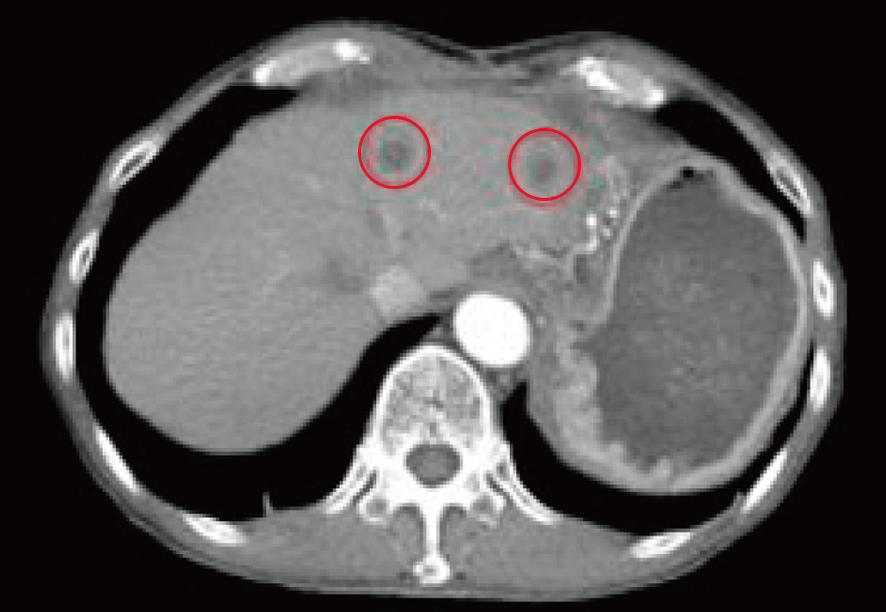

治療開始6カ月後のCT所見を示す。治療前には複数箇所に存在した転移性のがん腫瘍も肝臓の左葉に一部残存するのみで、治療は著効状態であった。

引き続きより一層の改善を目指し、内服治療の継続と経過観察を指示した。